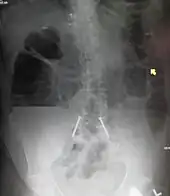

Upright abdominal X-ray demonstrating a small bowel obstruction. Note multiple air fluid levels. | |

Radiological signs of bowel obstruction include bowel distension and the presence of multiple (more than six) gas-fluid levels on supine and erect abdominal radiographs. Ultrasounds may be as useful as CT scanning to make the diagnosis.[17]